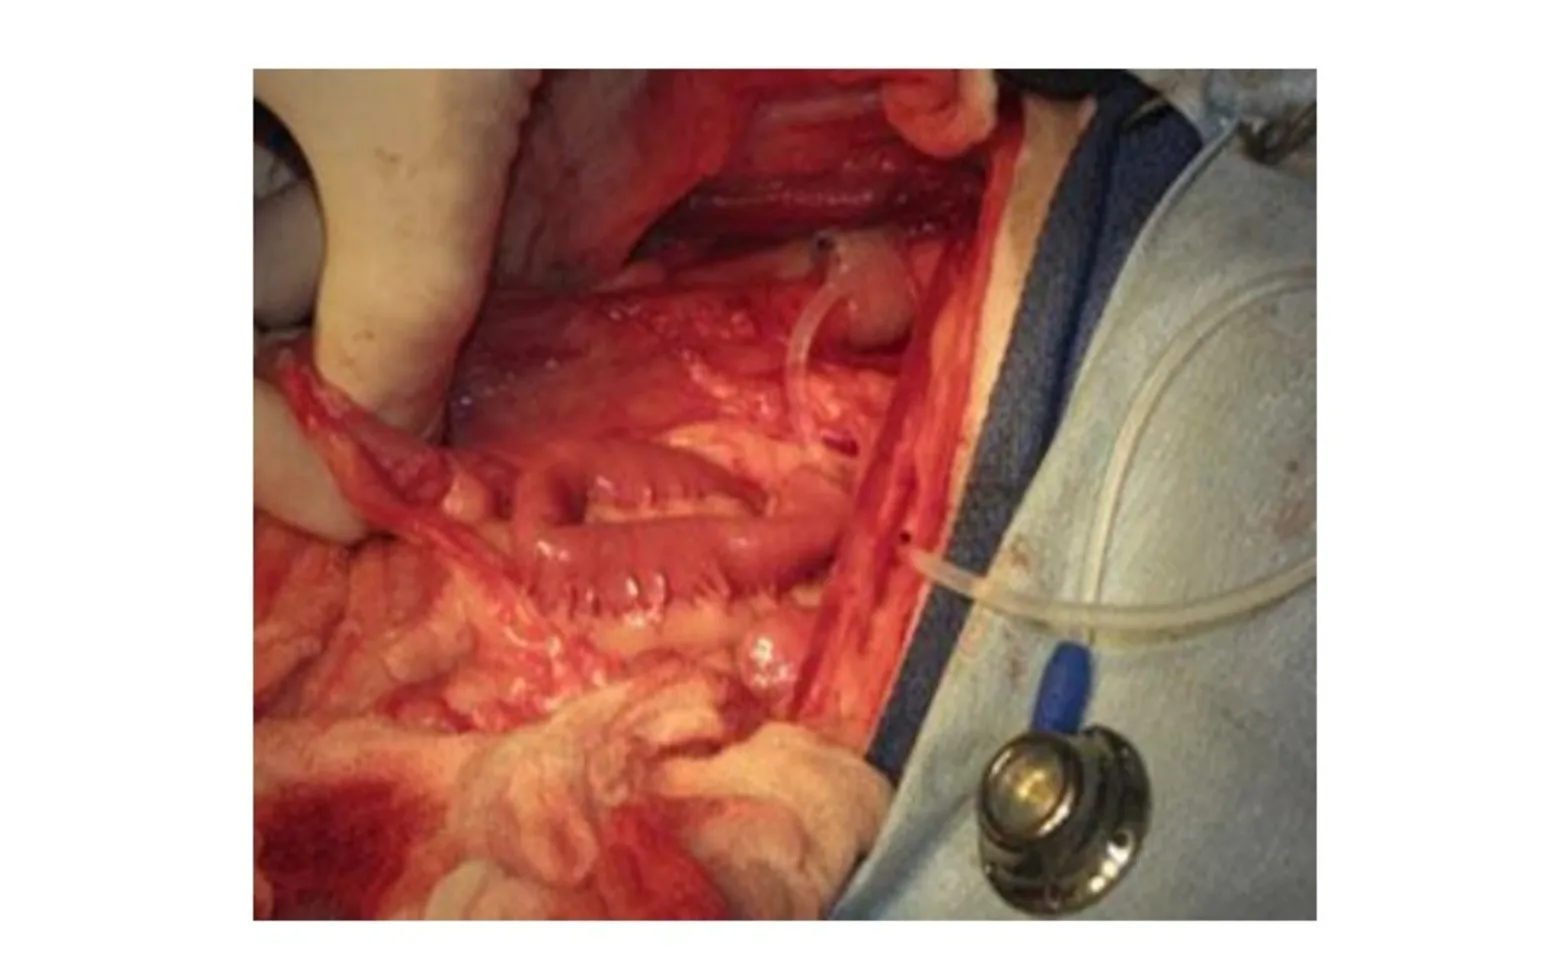

The most recent development in the control of USMI in dogs is implantation of artificial urethral sphincters. Artificial sphincters were developed for humans in the 1970s, and were used mainly for control of incontinence male patients after treatment for prostate cancer. Artificial sphincters have proven beneficial in humans who fail other treatments, but the cost of the sphincters (around $5000, plus $12,000-15,000 for implantation) has prohibited their use in veterinary medicine. In 2004, however, Adin and colleagues reported development of a static hydraulic urethral sphincter for use in dogs. The sphincter was constructed from a commercially available vascular occluder and subcutaneously implanted vascular access port, and could be obtained and inserted for a much more reasonable price than the previously available human products. The sphincter is placed around the urethra and the diameter can be adjusted by addition or removal of sterile saline through the vascular access port. Studies done in cadavers and in 4 clinical patients have shown promise, though there must be a good veterinarian-client-patient relationship, as recheck visits and frequent adjustment of the sphincter volume are often needed in the short-term post-op period.

Artificial sphincter in place. Courtesy Dr. James Flanders, Cornell University.